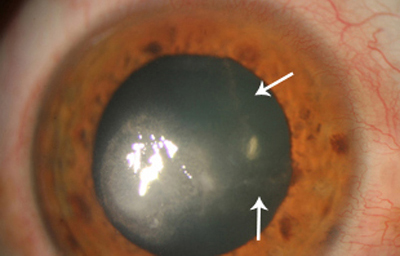

Superficie corneal irregular y grisácea, (Fig. 1, 2) con opácidades granulares en parche y formación de líneas epiteliales elevadas de aspecto granular (Fig. 3), que pueden arborizar dando imágenes de pseudodendritas. Opacidades superficiales satélites. (Figura 4) Inyección ciliar. Ulceración epitelial variante. (Figura 5).

Fig. 3 Líneas epiteliales elevadas. Síntomas de 40 días evolución